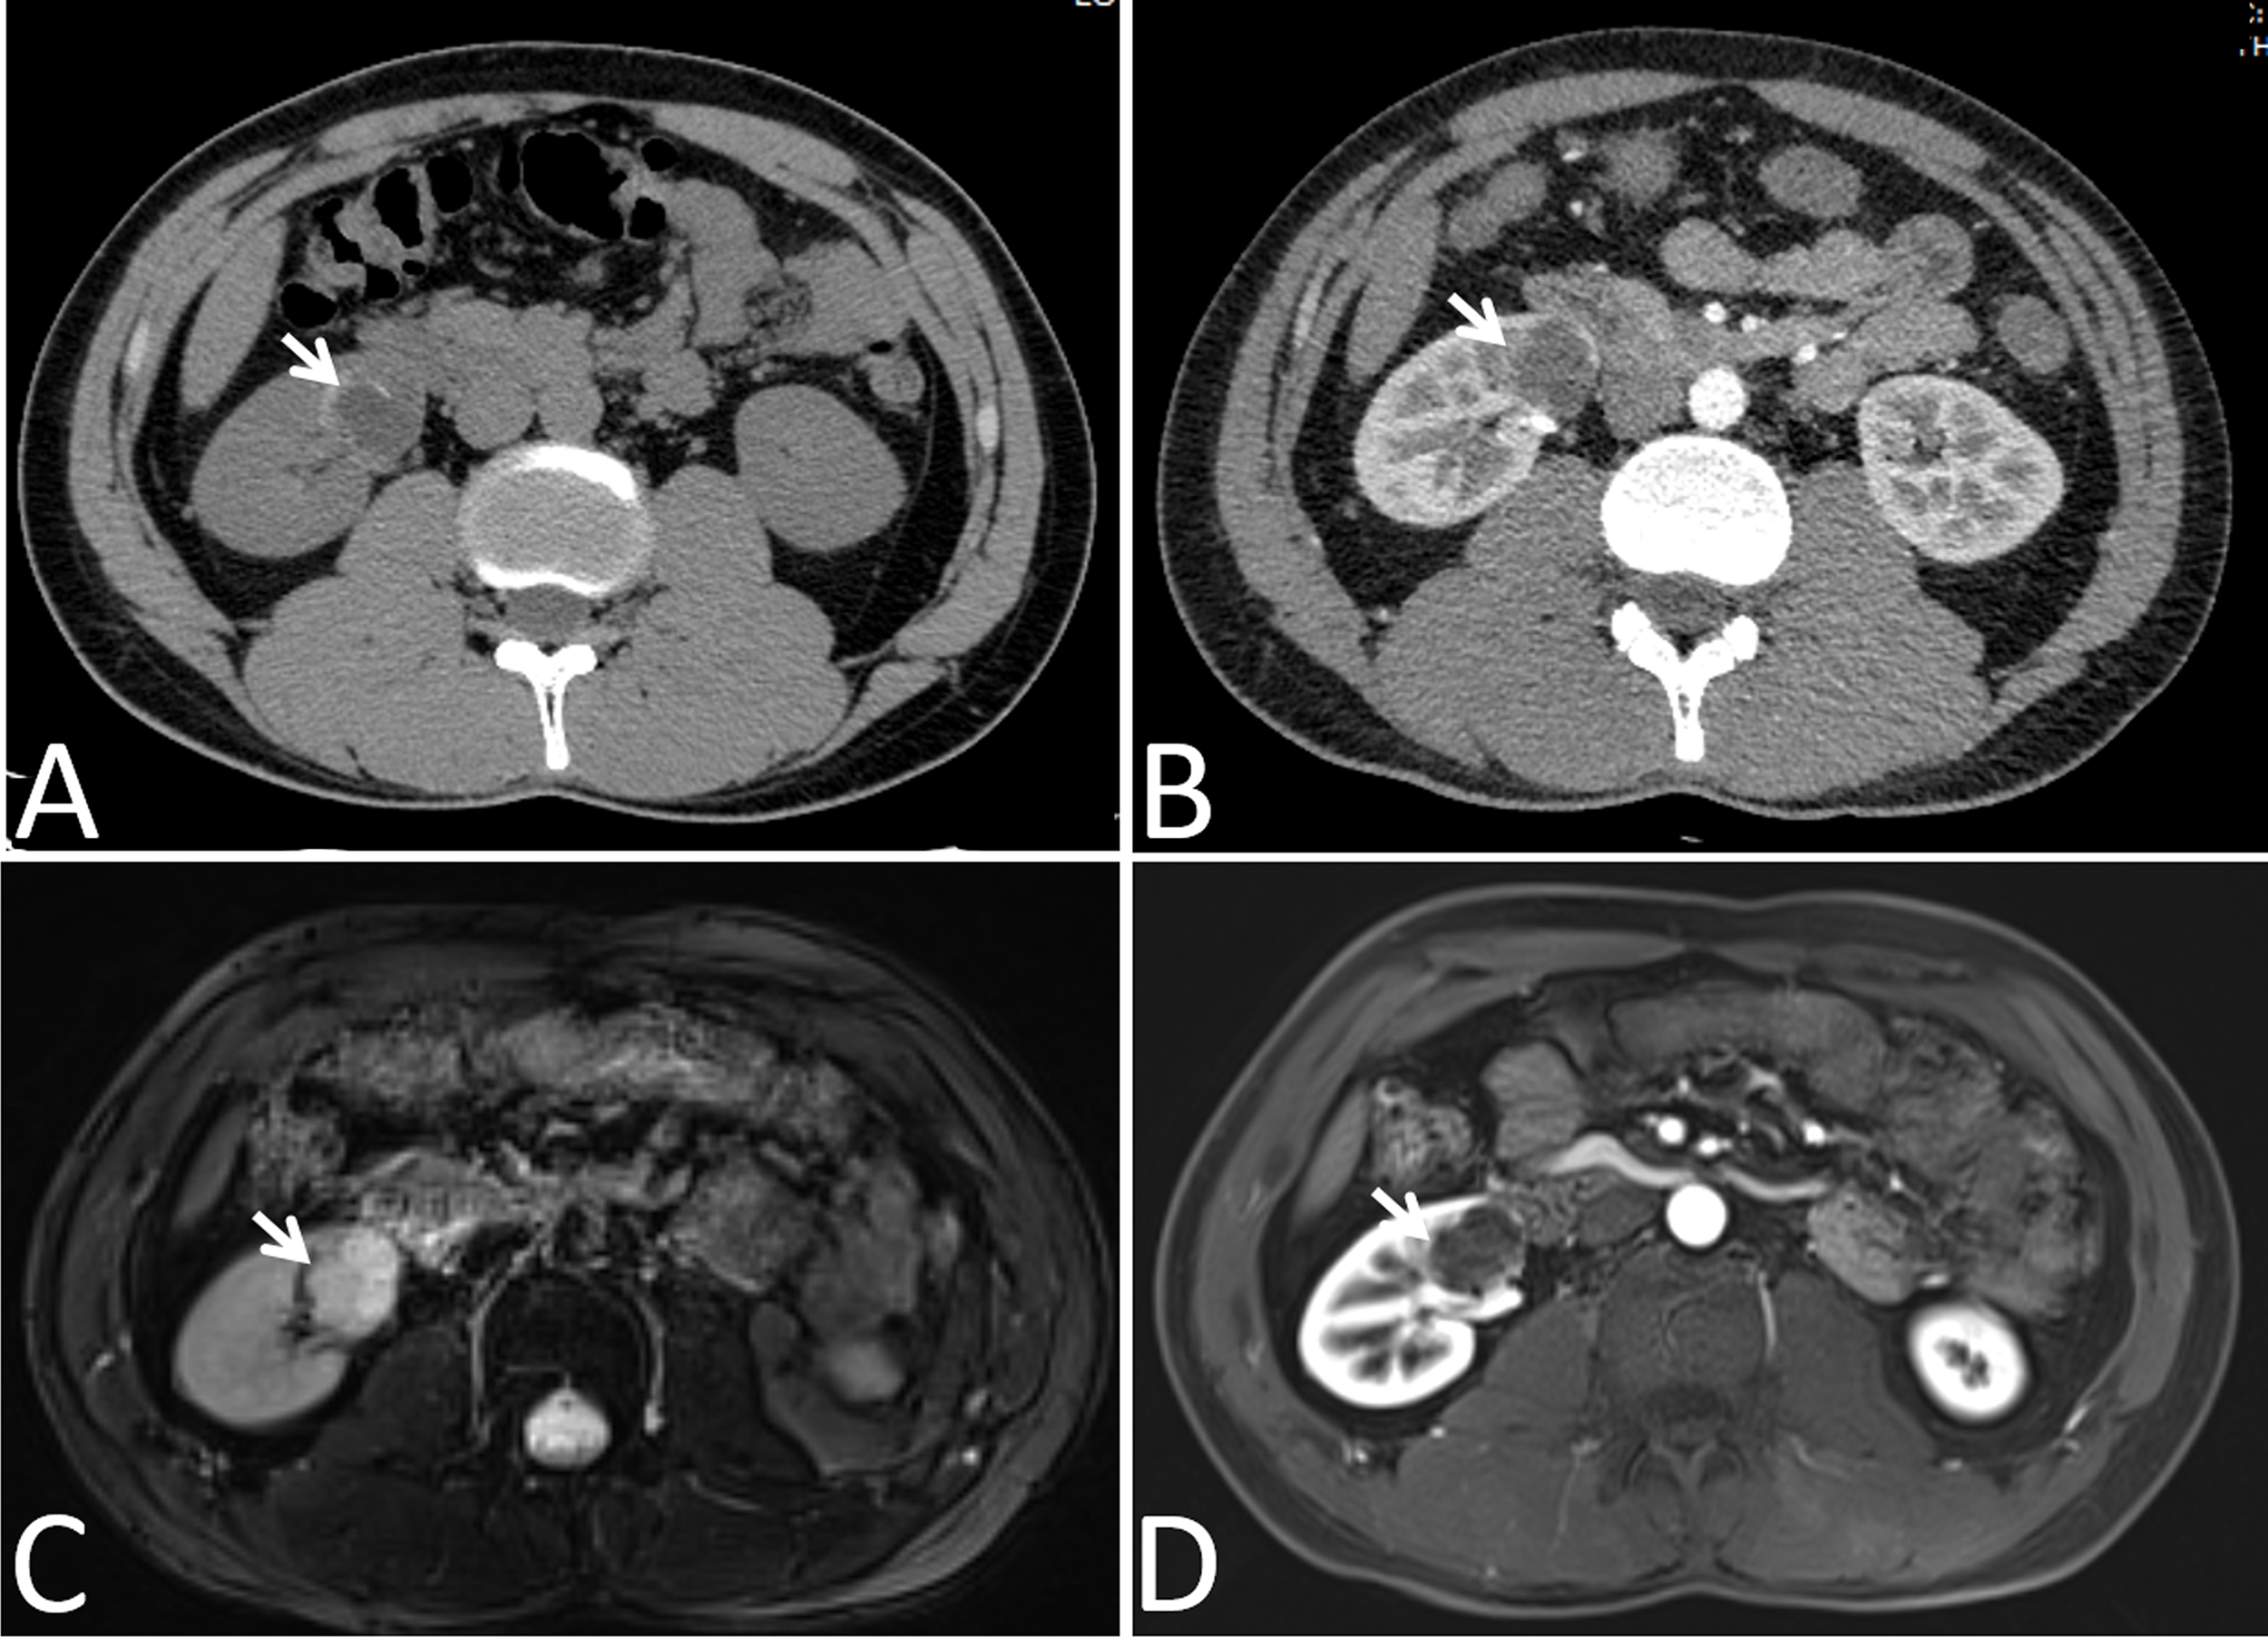

In our cohort, 87 lesions had both CT and routine MRI images, and MRI demonstrated more septa than did CT in 12 of 87 (13.8%) lesions (Figure 2). In one lesion, the cystic mass was classified as measurable enhancement of the wall on the enhanced CT because of the wall obscured by the high density calcification. Since calcification would not be depicted on the MRI, this suspected case of “pseudoenhancement” on CT has no measurable enhancement of the wall on enhanced MRI (Figure 3). Solid components of 13 cystic masses showed high signal intensity on DWI, all of which were malignant lesions (Figure 4).

Figure 3

Images in a 24-year-old man had a cyst with calcium deposits in the right kidney confirmed by pathology. (A) Axial non-contrast-enhanced CT image shown a cystic mass with thick crescent calcification (arrow) in its wall, (B) Axial contrast-enhanced CT image shown the wall of cyst was obscured by the high density calcification (arrow), (C) Axial T2-weighted MR image shown irregular thickening of the lesion wall (arrows), (D) Axial gadolinium-enhanced fat-suppressed T1-weighted MR image shown no measurable enhancement of the wall (arrows). Calcification depicted on the CT image was not mistaken for enhancement on the MR image.